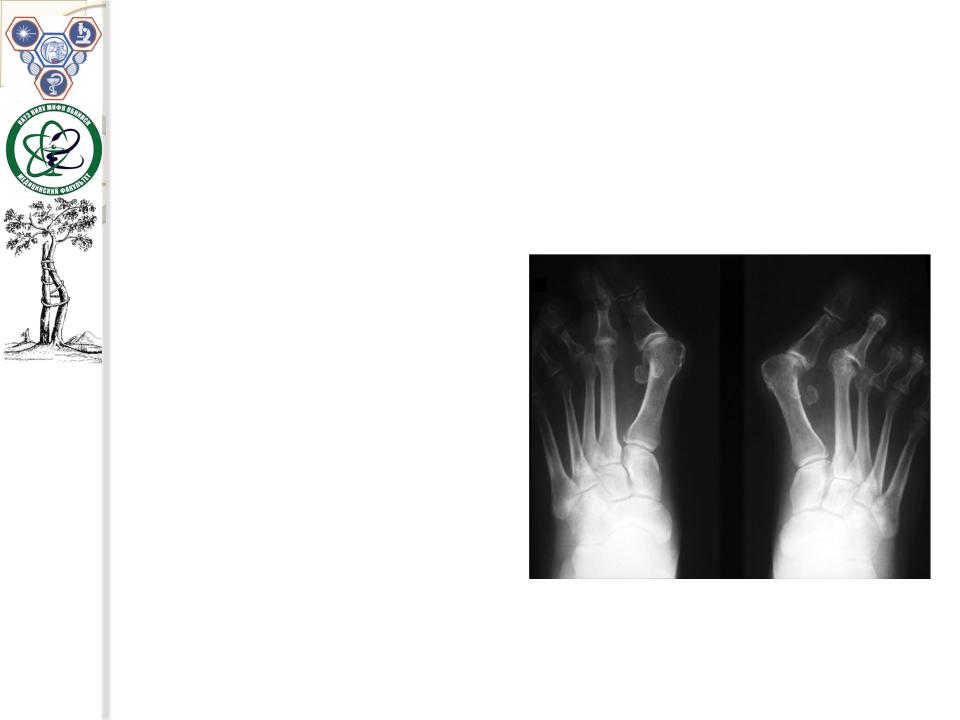

Деформирующийостеоартрозплюсно-фаланговогосустава большогопальцастопы

Обычнодвустороннийпроцесс.Больлокализуетсяповнутреннемукраю стопы.Данная формадеформирующегоостеоартрозазачастуюнеразрывно связанастакойизвестнойвортопедииформойдеформациистопыкак – Hallux valgus (вальгуснаядеформациябольшогопальцастопы).

Чаще всего вальгусная деформация большогопальца стопывстречается у женщин.Статистикаотмечает,чтона одногомужчину,страдающего этим заболеванием, приходитсядесятьженщин.

Этоможетбытьсвязано сгенетической илианатомическойпредрасположенностьюженщинкразвитиюданного состояния.

Ноосновойпричинойтакой«половой дифференцировки»этойпатологии, является, несомненно, стильобуви, которыйприсущженщинам – узкие носки ивысокие каблуки.

Вторичныйдеформирующий остеоартроз плюсно-фалангового сустава большого пальца стопычасторазвивается при подагре.